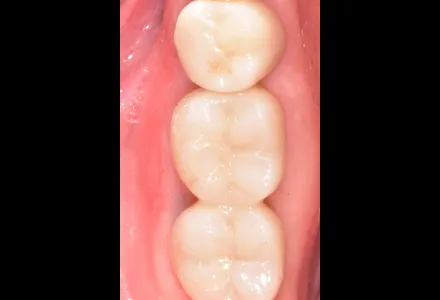

セラミック症例1

Before

After

- 治療名

- セラミックの詰め物

- 患者さん

- 30代 女性

- 執刀医

- 田中院長

- 治療

内容 - 今回は破折により形を失った右上前歯に対し、セラミックの詰め物を行いました。セラミックを被せることで見た目の自然さと機能性を回復しました。患者様から「前歯が欠けたときはとても落ち込みましたが、治療後は不安がなくなり、日常生活を明るく過ごせるようになりました。丁寧に治療してくださった田中院長に感謝しています。」とありがたいお言葉をいただきました。

- 治療期間

- 6ヶ月

- 治療費

- 800,000円〜

- リスク

- 強い力が加わると、割れたり欠けたりする可能性があります。